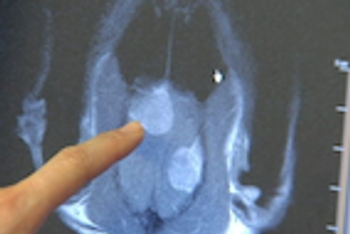

Thanks to a skilled neurosurgery team at Washington State University's Veterinary Teaching Hospital, a very lucky cat will be able to take advantage of all 9 of his lives.